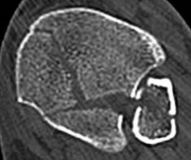

Fig 2.2-3a–h A CT scan with 3D reconstruction.

a–d Sagittal (a–b), coronal (c), and axial (d) images demonstrate displaced posterior, anterolateral, and medial fracture fragments resulting in intraarticular step and gap. The incongruent tibiotalar joint is best appreciated on the sagittal scan.

e–h The 3D reconstructed images show the external fracture anatomy and general alignment.